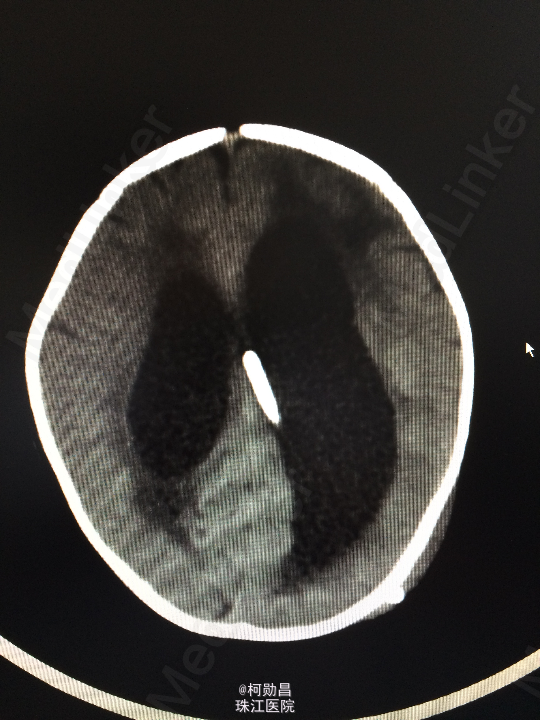

主诉:发热10天,抽搐3天 病史:患儿出生后8个月,因“发热10天,抽搐3天”入院,入院时体温39.3℃,神志不清,反应差。四肢肌张力增高,以双上肢肌力增高明显。病理征未引出。

查体:神志不清,四肢肌力增高 辅助检查:头颅CT提示脑积水并脑脊液外渗,幕上脑室扩张,右侧额颞叶硬膜下脑脊

诊断:化脓性脑膜炎伴脑积水 处理:予内科抗感染治疗,后行脑室腹腔引流术。